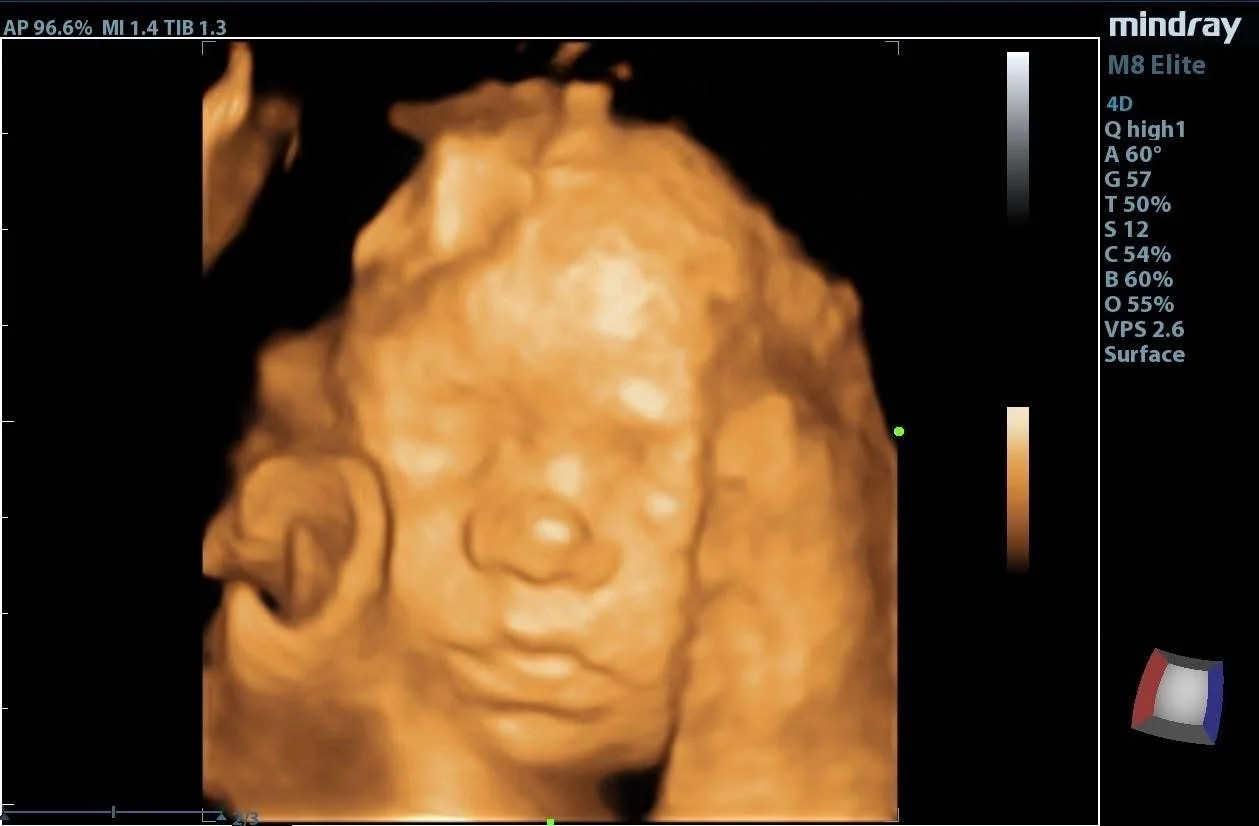

● 3D/4D Last Look 26-36 Weeks $100